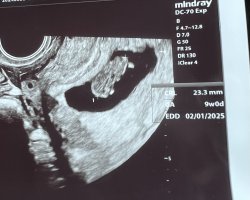

Vastoin kaikkia omia odotuksia, varhaisultrassa oli kaikki niin hyvin kuin tällä hetkellä mahdollista! Oviksesta laskettuna nyt ois 6+4 ja mittaamalla saivat 6+5 ja vahva syke löytyi 🩷

Iloisia uutisia siis, mutta jostain syystä ei puolison kanssa kumpikaan oikein osata iloita. Vähän jopa harmittaa, ettei oma pää jotenkin pysy tässä kaikessa ihan mukana. Mutta tärkeintä, että raskaus oli oikeasti alkanut, se oli kohdussa ja tällä hetkellä ainakin syke näkyi. Uskon ja toivon, että ilokin löytyy jos ja kun pidemmälle päästään. 🩷